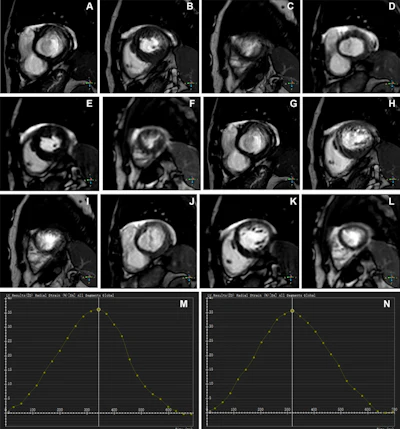

- MRI reveals how statins reduce vessel wall inflammationby Kate Madden Yee

null